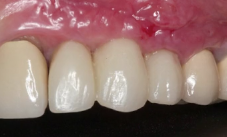

CLINICAL VIDEO Uncovering and Temporization of 2 Anterior Implants with Mucoging

CAT# CV-131

Uncovering and Temporization of 2 Anterior Implants with Mucogingival Surgery for optimal soft tissue healing

by Dr Sascha A Jovanovic

----

In this dental video by Dr Jovanovic a meticulous procedure involving the uncovering of two anterior implants with a mucogingival technique emplo... -